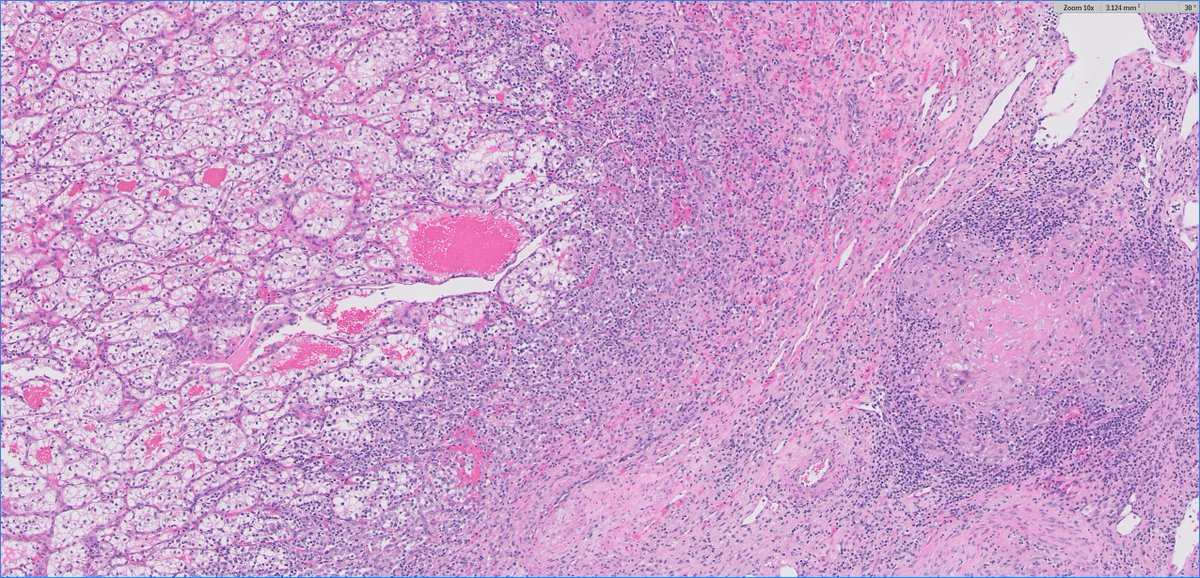

Uniquely intricate morphological pattern in #renal tumor! Catchy for #OnePicDx! 🔍 What is your diagnosis on this #nephrectomy #GUPath tweeps? Answer in comment👇👇👇